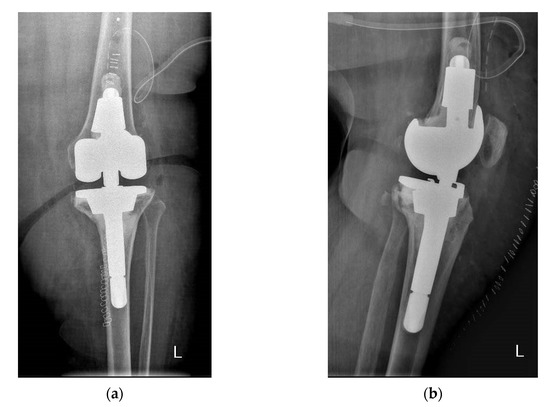

The number and type of stems and cones (Figure 2a,b) used for each group of patients are summarized in Table 5.

Figure 2. (a,b) Types of stems and cones utilized in revision TKA.